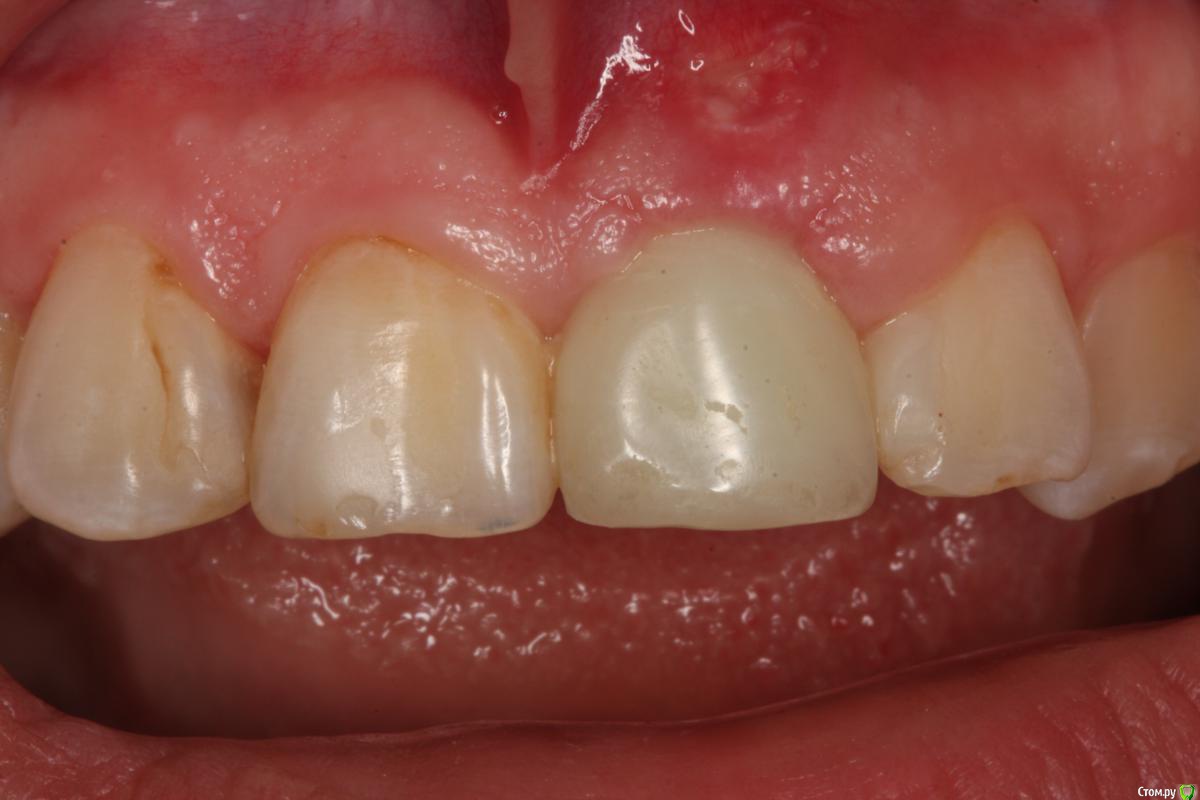

Zorrro Опубликовано 29 февраля, 2016 Автор Поделиться Опубликовано 29 февраля, 2016 (изменено) Через два дня пациент меня неприятно удивил.И ,безусловно,правильно было бы отменить операцию и ограничиться удалением,но… Вот такой был сюрприз под носом с нечищенными зубами.Обговорив риски,перекрестившись начали.Во время операции фото не делал.Слизистая в проекции 21 была сильно истончена острым гнойным процессом,буквально светилась.в итоге после эвакуации гноя промыл фурацилином,установил анкилос А11,подсыпал остеопласт вестибулярно и укрыл это всё сст из бугра в качестве мембраны.ещё один сст пошёл навременный абатмент в виде "шашлыка".Через 10 дней Через 4 месяцас рекомендацией замены пломбы на 12 у своего доктора мы ипопрощались.пациентка осталась глубоко удовлетворённой,а это главное. Изменено 29 февраля, 2016 пользователем Zorrro 4 Ссылка на комментарий